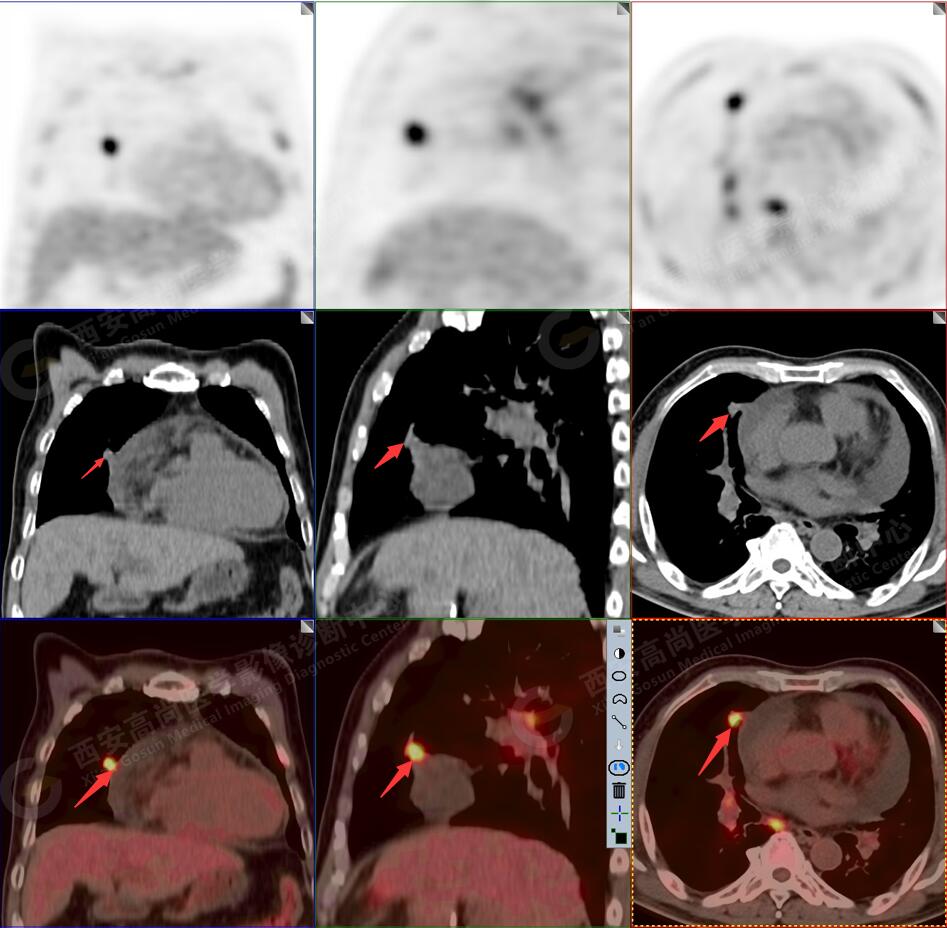

1.以下為肺內(nèi)原發(fā)灶

1.右肺中葉內(nèi)側段軟組織結節(jié),呈淺分葉狀,邊緣可見毛刺及胸膜牽拉征,呈FDG代謝異常增高,考慮為周圍型肺癌。